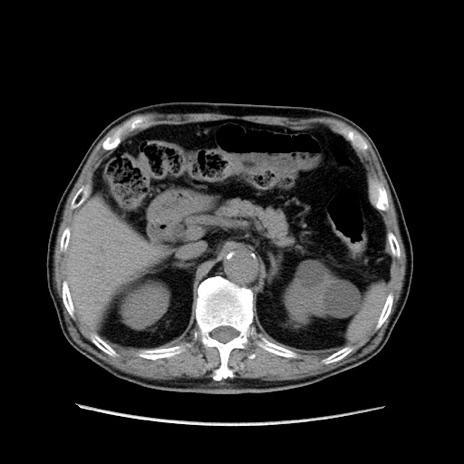

症例24(横断像)

【症例】80歳代男性

【主訴】左側腹部痛、嘔吐

【現病歴】本日早朝より左腹部に痛みあり。昼頃嘔吐認めたため、救急要請。

【既往歴】直腸癌(Mile手術)、胆摘

【身体所見】意識清明、BT 35.9℃、BP 221/93mmHg、SpO2 97%(RA) 、腹部:左ストーマ周囲に限局性の腹部膨隆あり。 膨隆部自発痛・圧痛あり・軟。

【データ】WBC 7700、CRP 0.09